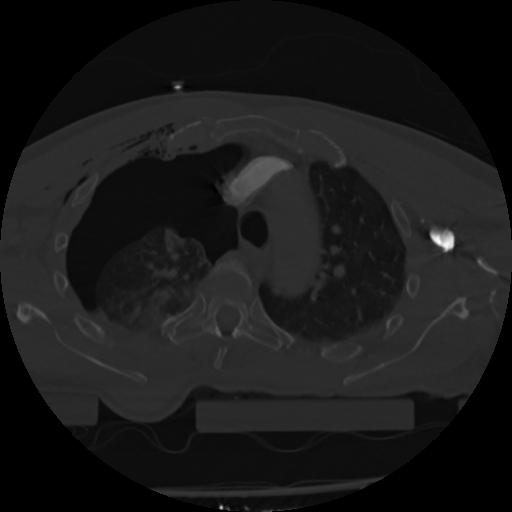

22 ANGIO,CE,Vol,0.5,ANGIO,,